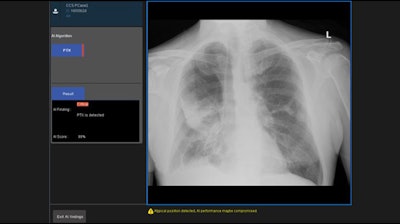

Canon Medical Systems is giving ECR 2020 attendees at look at digital radiography (DR) technology available through its subsidiary, Delft Imaging Systems, where a major focus is on developing software for tuberculosis (TB) screening, such as the CAD4TB computer-aided detection (CAD) application.

Although the World Health Organization has recommended systematic tuberculosis screening, many local regions lack the local expertise to read TB images, and thus incidence of the disease has not declined. CAD4TB can help by automatically detecting signs of TB for individuals who can then be sent on for additional definitive tests like the GeneXpert diagnostic assay.

CAD4TB is an algorithm that's been trained to detect pathology that's indicative of TB, such as diffuse textural patterns, focal patterns, and pleural-related abnormalities. The algorithm scans patient images and provides clinicians with a score that indicates the likelihood that a patient is infected with TB. Some 3 million people around the world have been scanned with CAD4TB, according to Canon.